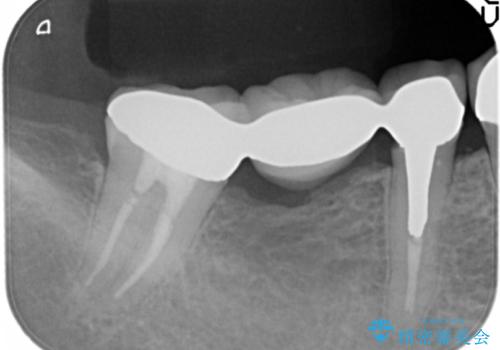

臼歯部メタルフリー再補綴

- 治療してからの年月が経過し、かみにくくなったブリッジ・クラウンを全てやりかえたいと希望され来院されました。

クラウン・ブリッジを作り替えるにあたり虫歯の徹底的な除去・根管治療のやり直しを行い今後やり直しをしなくて済むような環境を整えていきます。

装着して長期間経過したブリッジやクラウンは隙間から細菌が侵入し虫歯が再発してしまっていることがあります。

長期的に問題のないブリッジ・クラウンを作製するため、虫歯をしっかりと除去すること精密な根管治療を行うことが肝要です。